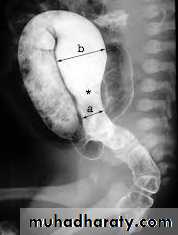

Barium enema :

(Narrow segment distally, transitional zone, dilated segment proximally).

Recto-sigmoid ratio less than 1 (transvers diameter of rectum / transverse diameter of sigmoid).

Retention of contrast material in the colon more than 24hr post filming.

Neonate with HD may have false –ve result.